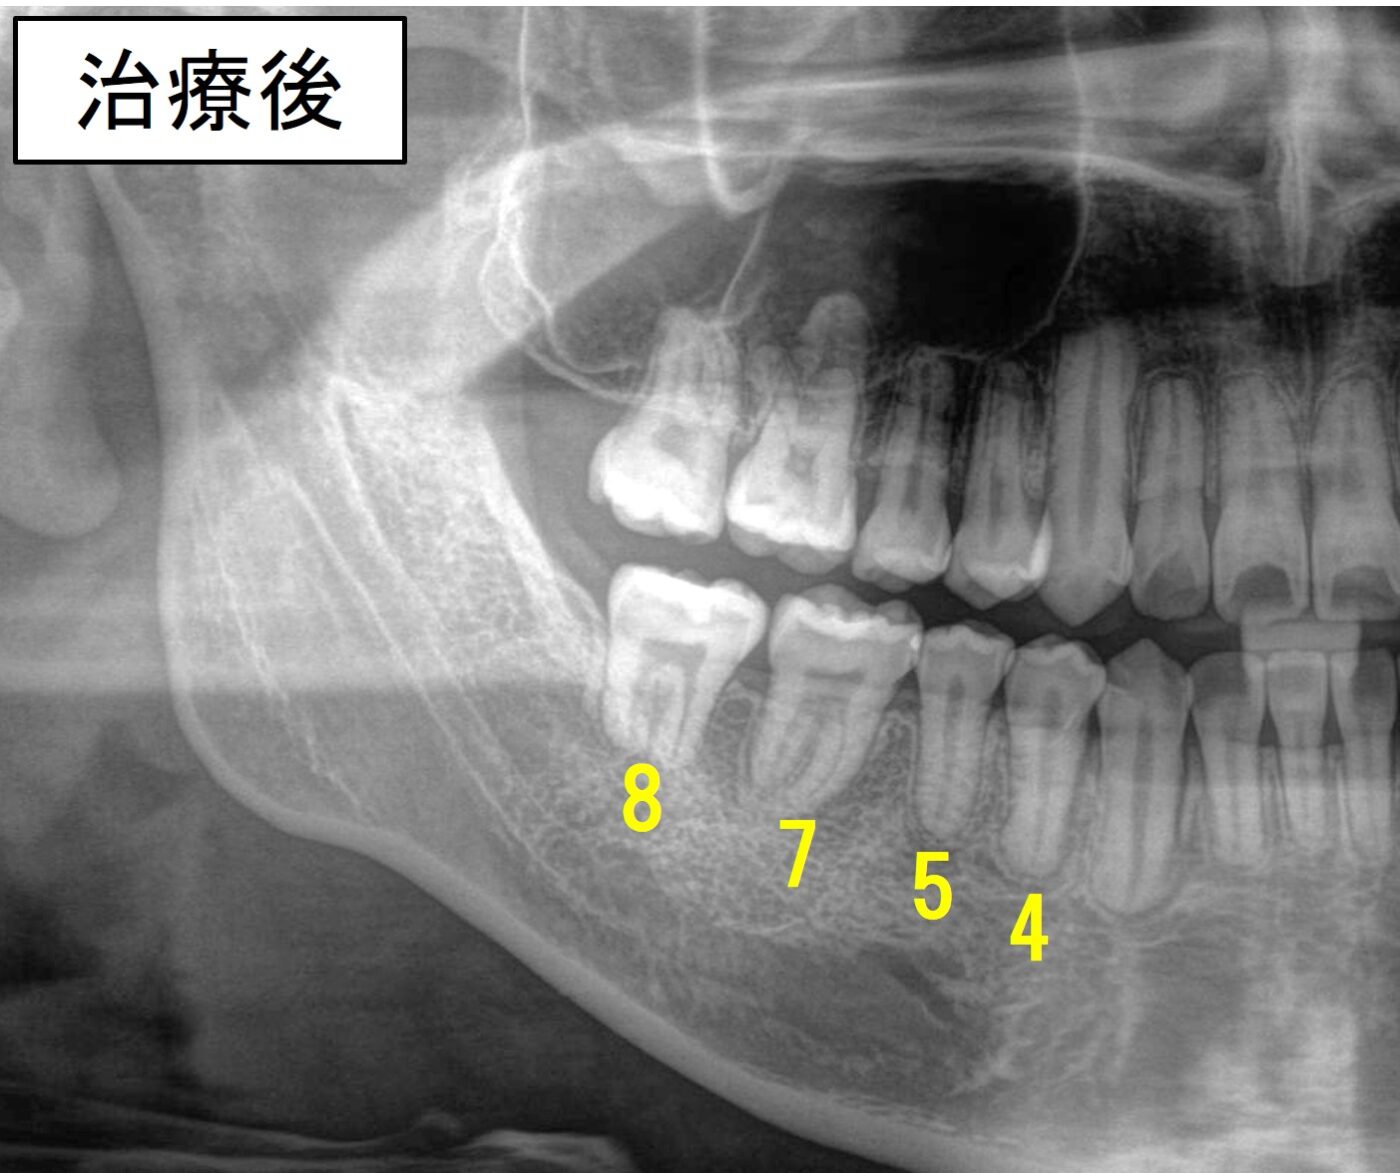

25歳ですが、7番を抜くと8番が自然に生えてきます。多少傾斜して生えるため、矯正治療で起こしながら手前に動かしました。

下の6番の位置があまり変化していないことに注目。

上下4・5番の位置関係があまり変化していないことに注目。

今回は、7番を抜歯して自然と8番が生えてきたため、左下8番を移動させるのに、歯科矯正用アンカースクリューを用いるほどではありませんでした。

「根管治療歯の7番を残して矯正、将来的に抜歯→インプラント」と言う流れを断ち切ることができた。

天然歯のみで奥歯の咬み合わせを再構築

治療期間は通常より延長(約3年6か月)

このように、条件がそろえば 親知らずは「抜く歯」ではなく「使える歯」 になります。